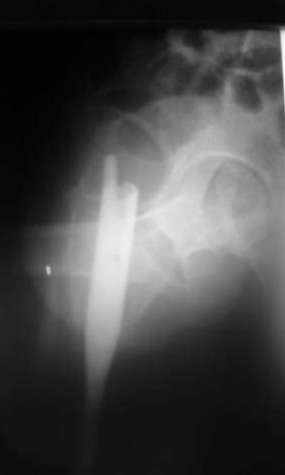

Мы закончили репозицию отломков бедренной кости в аппарате (рис. 1, 2) у нашей пациентки (http://weborto.net/forum/1200869039/index_html) и на прошлой неделе сделали ей вторую операцию. Штифт удалось ввести закрыто. Верхний шеечный винт держался очень плохо, поэтому мы его убрали и решили не ставить. Нижний держал очень плотно. Рентгенограммы после операции прилагаю (рис. 3,4). Пока не получилось сделать нормальный аксиальный снимок (больная с трудом сгибает и отводит ногу в тазобедренном суставе). Пока сделали боковую проекцию в положении на здоровом боку со сгибанием здоровой ноги.

Имя     : рис. 3.jpg

Тип     : image/jpeg

Размер  : 19378 байтов

Описание: отсутствует

Url     : http://weborto.net:8080/pipermail/ortho/attachments/20080216/c8b24fe3/attachment-0006.jpg